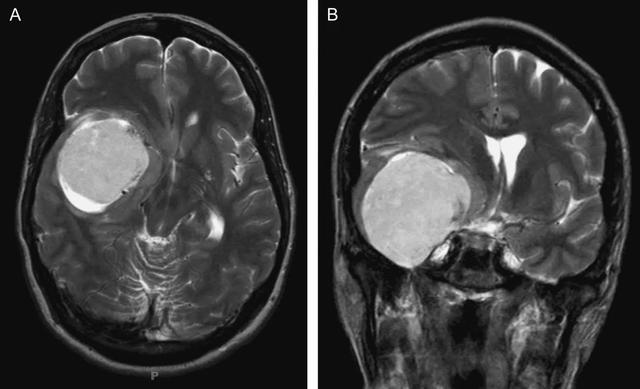

患者MR检查结果显示其右侧桥小脑角区有占位;头部CTA显示占位区附近有大部分钙化。较终,李阿姨被诊断为右侧桥小脑角区脑膜瘤。

随后,经过INC国际神经外科医生集团的协调,李阿姨及其女儿前往德国接受巴特朗菲教授的治疗。巴特朗菲教授为患者行右侧桥小脑角区脑膜瘤切除术,将一颗像橡胶一样坚硬、番茄般大小的瘤子从患者脑中完全切除了。

桥小脑角区脑膜瘤是指位于脑内岩骨后表面和附近的硬脑膜,包括起源于岩骨后或侵及小脑幕的脑膜瘤。此类脑膜瘤的质地通常会比较坚硬。